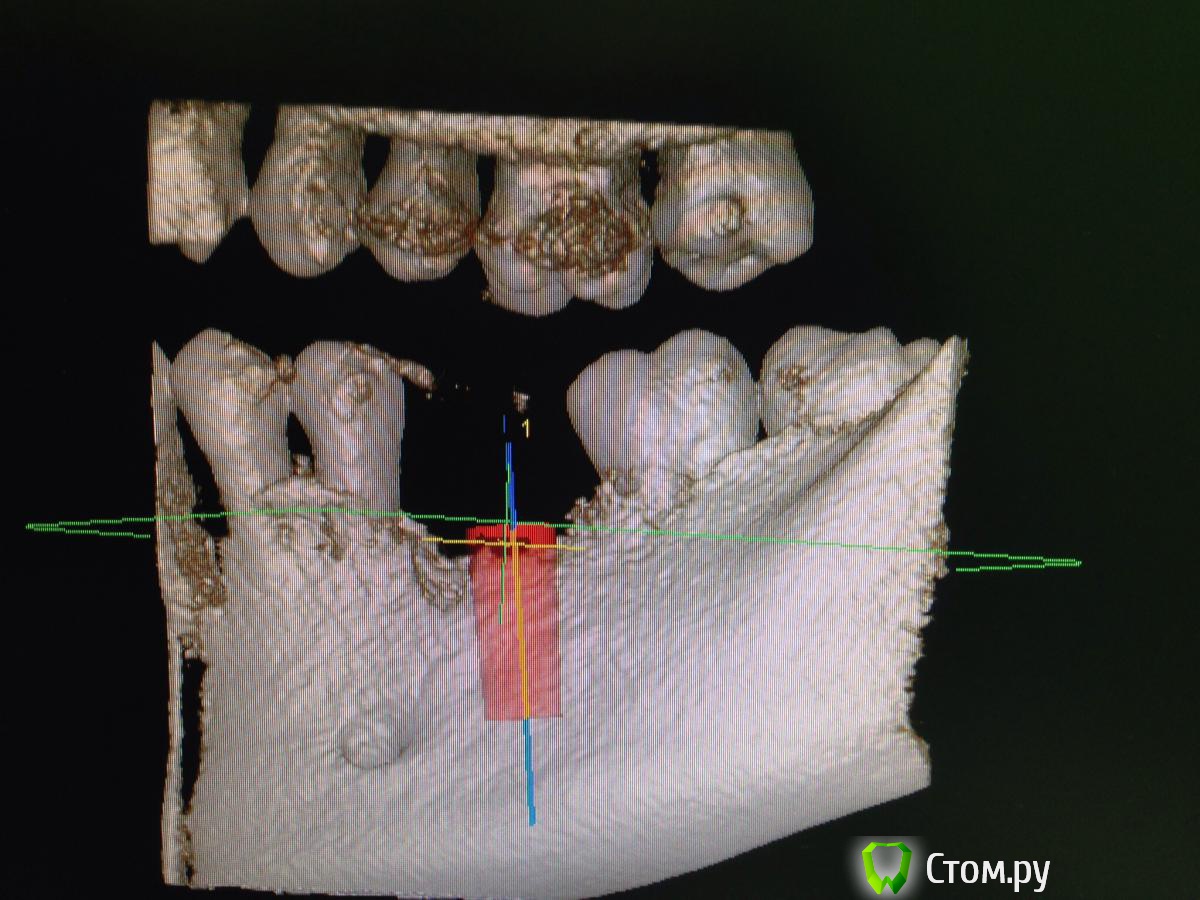

diesel87 Опубликовано 10 февраля, 2014 Поделиться Опубликовано 10 февраля, 2014 Планируется установка винта в области удаленного 3 месяца назад 36 зуба, размером 4,8*12; вот срезы кт, винт планирую в такой позиции, волнует костная пластика, нужна ли она и где именно и не слишком ли глубоко будет стоять винт по отношению к соседним зубам? Ссылка на комментарий

Acidrocker Опубликовано 10 февраля, 2014 Поделиться Опубликовано 10 февраля, 2014 имхо, на миллиметр еще можно заглубить.. по ширине, может, лучше что-нибудь около 4,0-4,3? Ссылка на комментарий

diesel87 Опубликовано 10 февраля, 2014 Автор Поделиться Опубликовано 10 февраля, 2014 На мм углубить думаю судя уже по высоте на операции, но не будет ли слишком глубоко? Можно ли сделать так чтоб оставить немного по высоте не в кости и засыпать графтом и мембраной укрыть? А по поводу диаметра, 4,3 советуете исходя из толщины межкорневой перегородки? Ссылка на комментарий

Maxfac Опубликовано 10 февраля, 2014 Поделиться Опубликовано 10 февраля, 2014 (изменено) На мм углубить думаю судя уже по высоте на операции, но не будет ли слишком глубоко? Можно ли сделать так чтоб оставить немного по высоте не в кости и засыпать графтом и мембраной укрыть? А по поводу диаметра, 4,3 советуете исходя из толщины межкорневой перегородки?А что за систему хотите ставить? По мне, вариант с графтом и мембраной - от лукавого. Ставьте вровень, это не то "глубоко", из-за которого стоило бы париться) Изменено 10 февраля, 2014 пользователем Maxfac 1 Ссылка на комментарий

Acidrocker Опубликовано 10 февраля, 2014 Поделиться Опубликовано 10 февраля, 2014 На мм углубить думаю судя уже по высоте на операции, но не будет ли слишком глубоко? Можно ли сделать так чтоб оставить немного по высоте не в кости и засыпать графтом и мембраной укрыть? А по поводу диаметра, 4,3 советуете исходя из толщины межкорневой перегородки?4.5 или даже 4.0, исходя из количества кости вокруг шейки. на имплантиуме пришеечная резорбция бывает достаточно выражена. не надо графт и мембрану, если можно заглубить на мм) 1 Ссылка на комментарий

diesel87 Опубликовано 10 февраля, 2014 Автор Поделиться Опубликовано 10 февраля, 2014 4.5 или даже 4.0, исходя из количества кости вокруг шейки. на имплантиуме пришеечная резорбция бывает достаточно выражена. не надо графт и мембрану, если можно заглубить на мм)4.5 или даже 4.0, исходя из количества кости вокруг шейки. на имплантиуме пришеечная резорбция бывает достаточно выражена. не надо графт и мембрану, если можно заглубить на мм)Толщина кости 8 мм, а графт и мембрану я больше вестибулярно хотел положить, там провальчик не большой есть, а что по поводу резорбции вокруг Implantium? Ссылка на комментарий

Sahan Опубликовано 10 февраля, 2014 Поделиться Опубликовано 10 февраля, 2014 Платформу на 1 мм заглубить, соотношение будет самое оно . Имплантат лучше 4,2на 10мм, хотя 4,8 тоже сойдет 1 Ссылка на комментарий

Sahan Опубликовано 10 февраля, 2014 Поделиться Опубликовано 10 февраля, 2014 Учитывая что Вам нужно на 1 мм утопить имплантат, а на крайнем фото до канала осталось около 2 мм, 12 мм будет впритык к каналу. Что , как писал коллега выше, может боком вылезти. Ссылка на комментарий